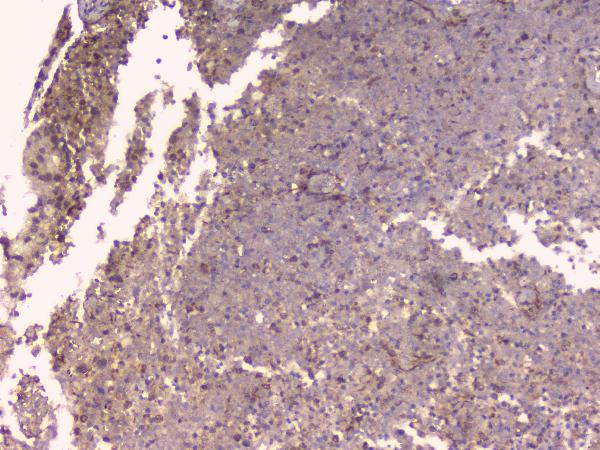

IHC analysis of OPG/TNFRSF11B using anti-OPG/TNFRSF11B antibody (A00863).

OPG/TNFRSF11B was detected in a paraffin-embedded section of human tonsil tissue. Biotinylated goat anti-rabbit IgG was used as secondary antibody. The tissue section was incubated with rabbit anti-OPG/TNFRSF11B Antibody (A00863) at a dilution of 1:200 and developed using Strepavidin-Biotin-Complex (SABC) (Catalog # SA1022) with DAB (Catalog # AR1027) as the chromogen.